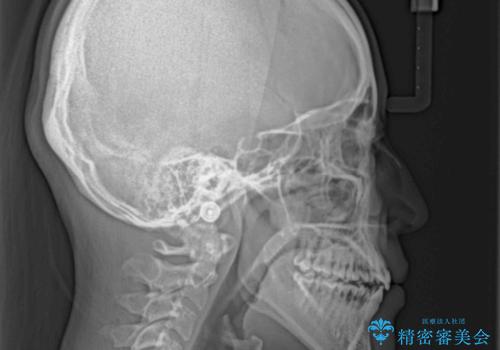

上顎骨を拡大することで、八重歯やデコボコを歯列に収めることができ、下顎の歯が外に位置していた奥歯の咬み合わせも改善することができました。

スペースも短期間に獲得できるため、1年程度で治療を終えることができました。